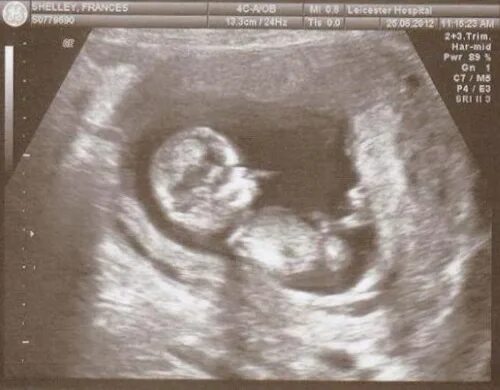

Беременность беременна 18 недель